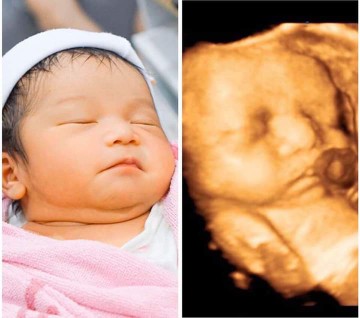

ซาว์4มิติ

ซาว์4มิติ เราสามารถซาว์ได้ตอนน้องกี่เดือนคะ ไม่ทราบจริงๆคะ ท้องแรก

บ้านนี้ซาวน์ตอน8เดือน เพื่อดูหน้าน้องก่อนคลอดค่ะ

6-7เดือนค่ะกำลังดี